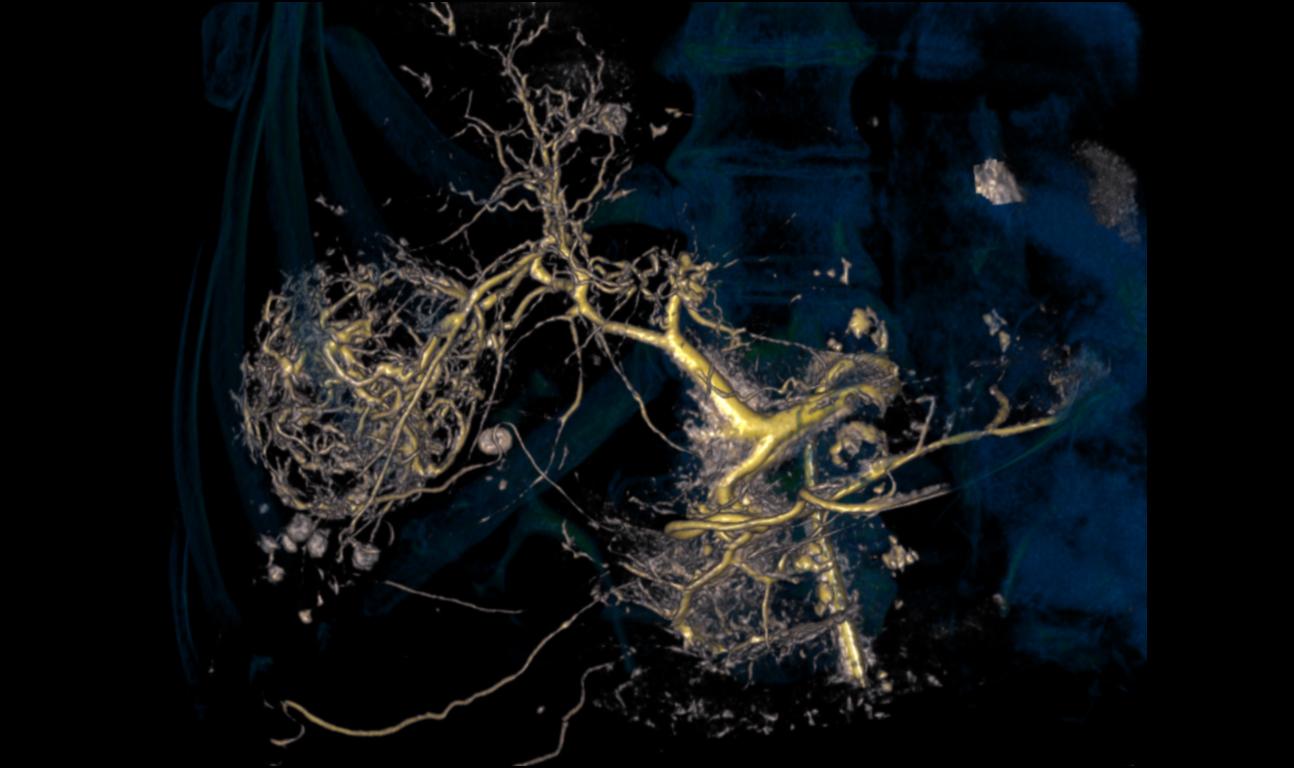

Material-specific imaging with Structure Scout

Structure Scout enables improved device visibility supporting ALARA dose due to material-specific optimization of imaging parameters.

With new devices and new materials appearing all the time, image-guided therapy is facing new challenges. Structure Scout adjusts the X-ray spectrum to material-specific acquisition parameters and optimizes visibility of materials, devices, vessels, and background structures independent of procedure or material type with our embedded structure-sensitive algorithm.